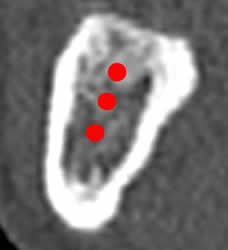

Fig 29. Densidad ósea.

TAC reconstrucción transversal. Varias mediciones de la densidad ósea, sobre el trayecto del implante.